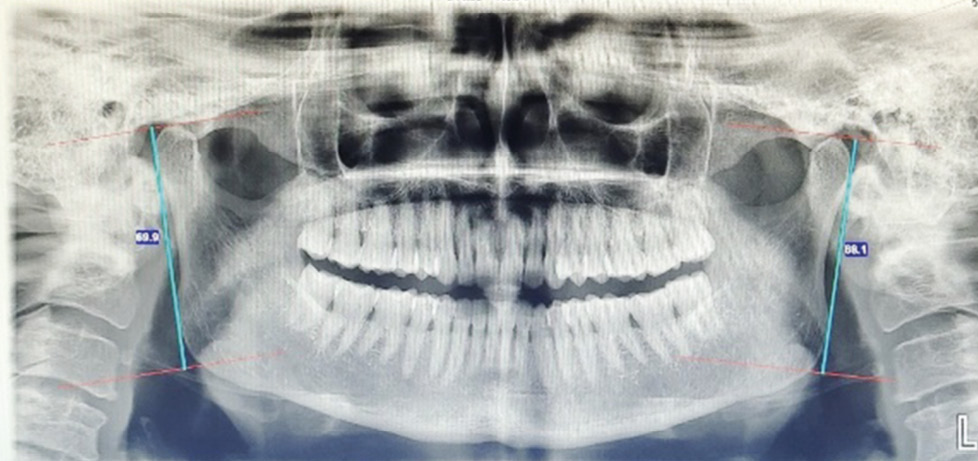

Fig. 1. Bilateral angular measurement of the gonial angle.

It is formed by drawing a line between two imaginary lines that extend from lower border of the mandible to ramus of the mandible.